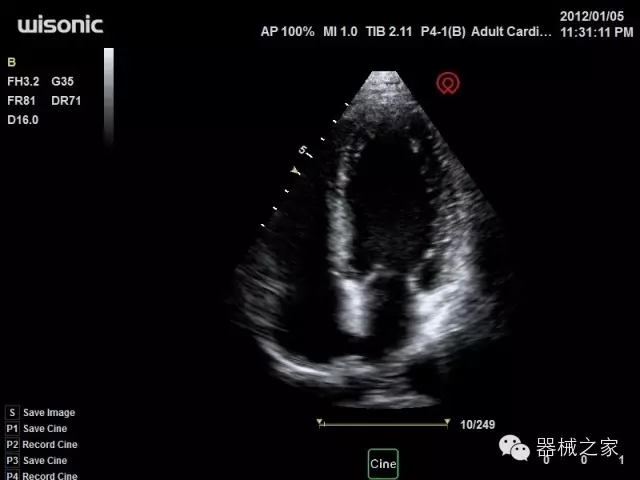

臨床圖片賞析

·全球目前唯一一款配備主機(jī)雙探頭接口,整機(jī)重量(含電池)在5公斤以內(nèi)的便攜式彩超;